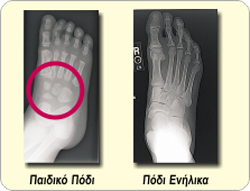

Η σωστή μέτρηση του ποδιού είναι ιδιαίτερα σημαντική στο παιδικό πόδι για τους εξής λόγους:

Το παιδικό πόδι δεν διαθέτει ακόμα τα 26 οστά όπως το πόδι ενός ενήλικα αλλά περιέχει εύπλαστους χόνδρους οι οποίοι χρειάζονται πολλά χρόνια μέχρι να μετατραπούν σε οστό.

Τα ποδαράκια των παιδιών είναι τόσο εύκαμπτα που χωράνε με εντυπωσιακή «άνεση», ακόμη και σε υπερβολικά στενά παπούτσια. Τα παιδιά δεν υποφέρουν καθόλου και συνεπώς δεν διαμαρτύρονται!

Η οστεοποίηση στο παιδικό πόδι δεν ολοκληρώνεται πριν την ηλικία των 18-20 ετών και μέχρι τότε, τα οστά και οι αρθρώσεις παραμορφώνονται εύκολα όταν υποβάλλονται σε υπερβολική πίεση από τα στενά παιδικά παπούτσια!